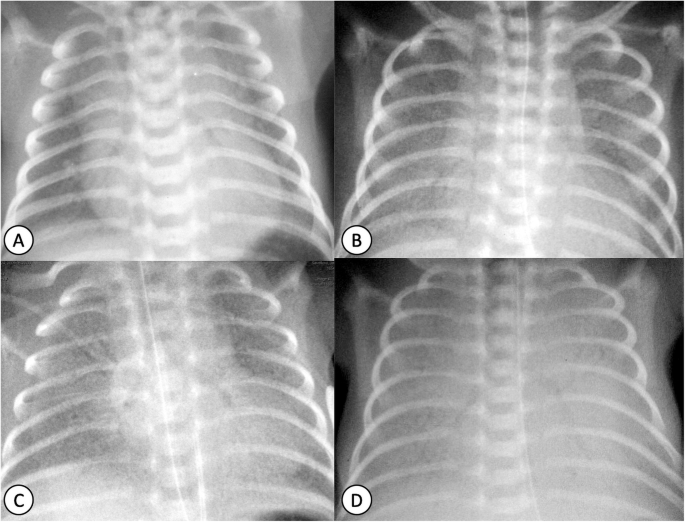

Основа диагностики респираторного дистресс-синдрома — анамнез и характерные рентгенографические признаки, которые позволяют отличить его от других распространенных неонатальных легочных заболеваний. Они варьируют от гипоинфляции, диффузных гранулярных помутнений до «белых легких» с воздушной бронхограммой и двусторонним признаком силуэта. Классификация, которую используют рентгенологи при описании снимков, то есть градация от 1 до 4 (рисунок 15), отличается от подхода неонатологов. Они предпочитают выделять тяжесть РДС как легкую, умеренную или тяжелую — основываясь на визуализации контуров сердца на рентгенограмме.

Рисунок 1. Градация респираторного дистресс-синдрома на рентгенограммах грудной клетки. (A) РДС I степени: матовое стекло с хорошо расправленными легкими и ограниченными воздушными бронхограммами; (B) РДС II степени: более выраженное помутнение легких, которые относительно хорошо расправлены, количество воздушных бронхограмм увеличено; контуры сердца и диафрагмы все еще хорошо очерчены; (С) РДС III степени: грубозернистое помутнение легких и менее отчетливый силуэт сердца и диафрагмы, распространенные воздушные бронхограммы и плохо расправленные легкие; (D) РДС IV степени: полный коллапс легких с полным помутнением, нечетким силуэтом сердца и легких, распространенные воздушные бронхограммы

Типичные осложнения РДС — пневмоторакс и интерстициальная эмфизема легких, которую вызывает утечка воздуха, связанная с баротравмой при механической вентиляции. При визуализации на рентгенограмме она выглядит как округлые или трубчатые перигилярные просветы — интерстициальные воздушные пузырьки. После введения экзогенного сурфактанта наблюдают улучшение — увеличение вентиляции легких и уменьшение помутнений, несмотря на то, что гипоинфляция и гранулярные помутнения могут сохраняться.